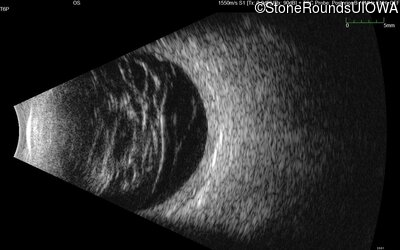

B-Scan Ultrasonography - Right - 20/300 sc

Exemplar

B-Scan Ultrasonography - Left - 20/200 sc